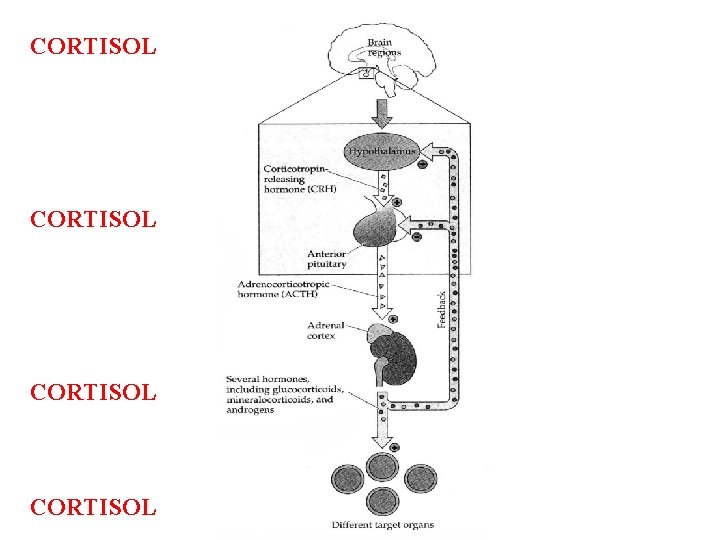

CORTISOL

1. cortisol goes up with novelty, uncertainly, threat, conflict, unpredictability, pain, maternal separation 2. cortisol=kills hippo= bad memory and kills PFC= short term memory in depression bad decisions under stress; robs hippo of glucose=toxic effect of glutamate-Cushing’s disease 3. cortisol highest AM and lowest 12 hrs later 4. depression=loss diurnal cortisol levels; elevated Amyg hypo